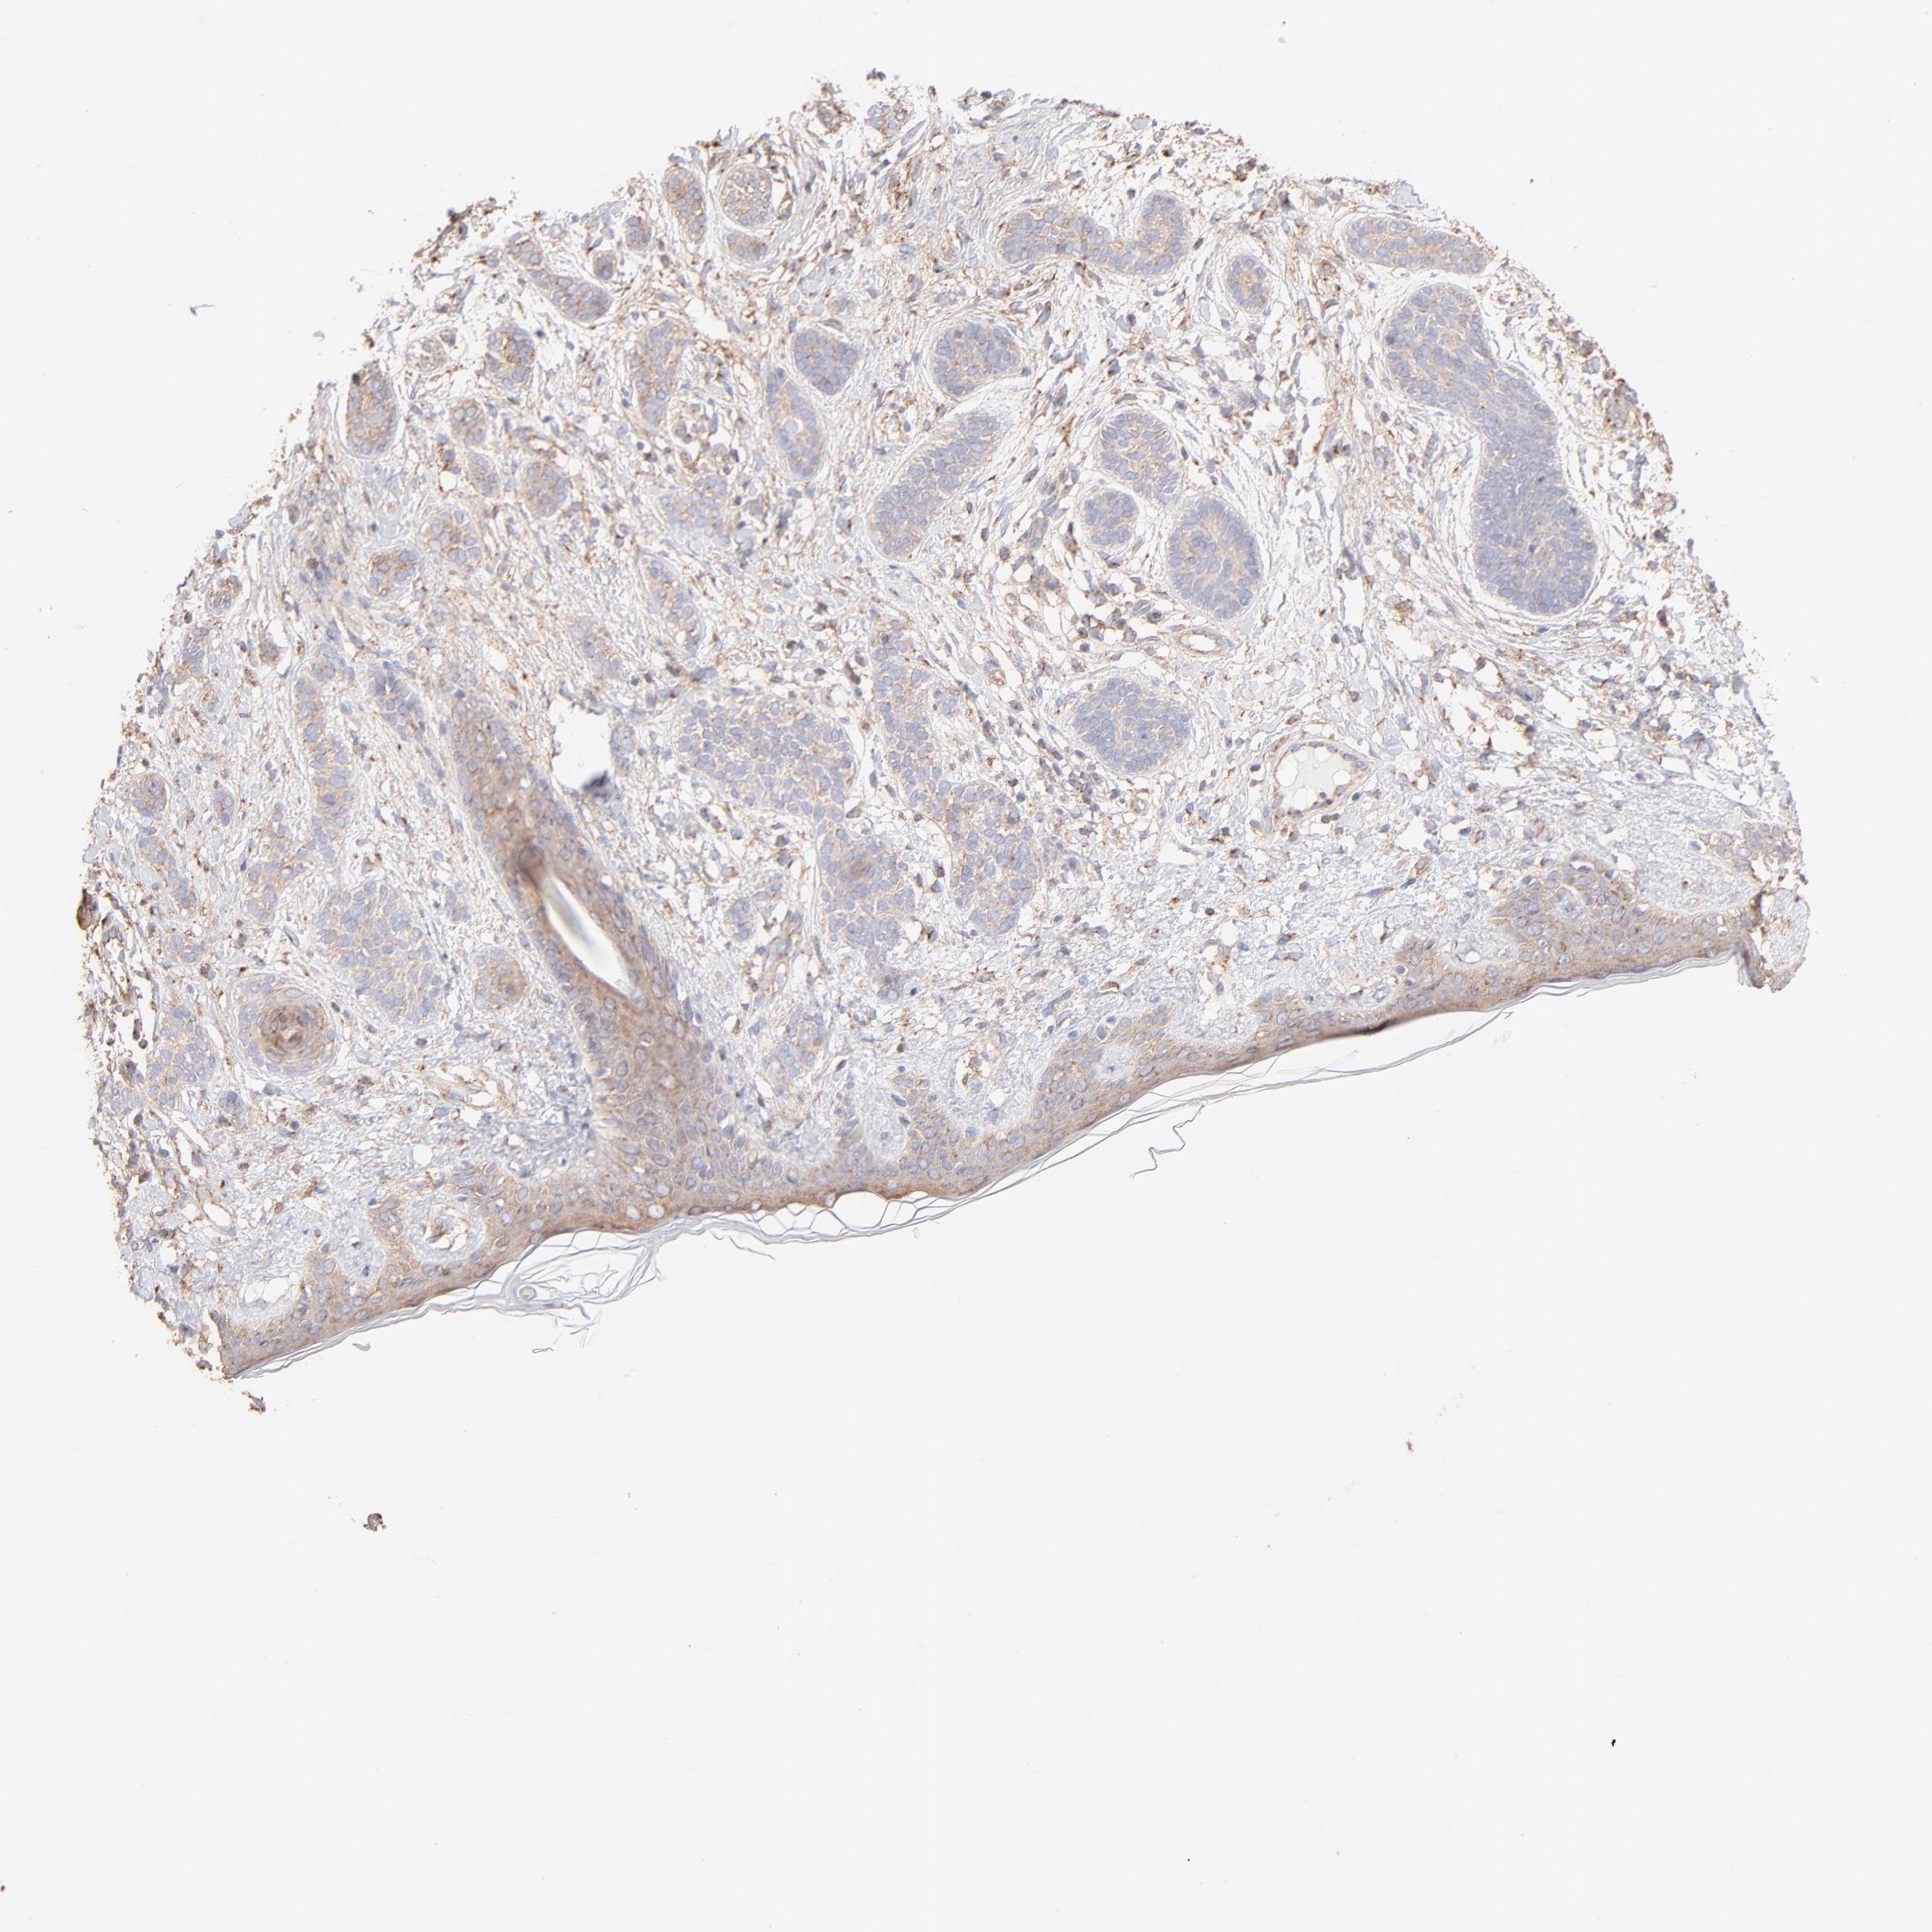

Basal cell and squamous cell cancer

SKIN CANCER - Protein expressioni

A mouse-over function shows sample information and annotation data. Click on an image to view it in a full screen mode. Samples can be filtered based on level of antibody staining by selecting one or several of the following categories: high, medium, low and not detected. The assay and annotation is described here.

Antibody stainingi

Antibody staining in the annotated cell types in the current human tissue is reported as not detected, low, medium, or high, based on conventional immunohistochemistry profiling in selected tissues. This score is based on the combination of the staining intensity and fraction of stained cells.

Each image is clickable and will lead to virtual microscopy that enables deeper exploration of all samples and also displays staining intensity scores, fraction scores and subcellular localization as well as patient and tissue information for each sample.

Antibody CAB003692

Staining

Medium

Weak

75%-25%

Location

Cytoplasmic/membranous,nuclear

Basal cell carcinoma